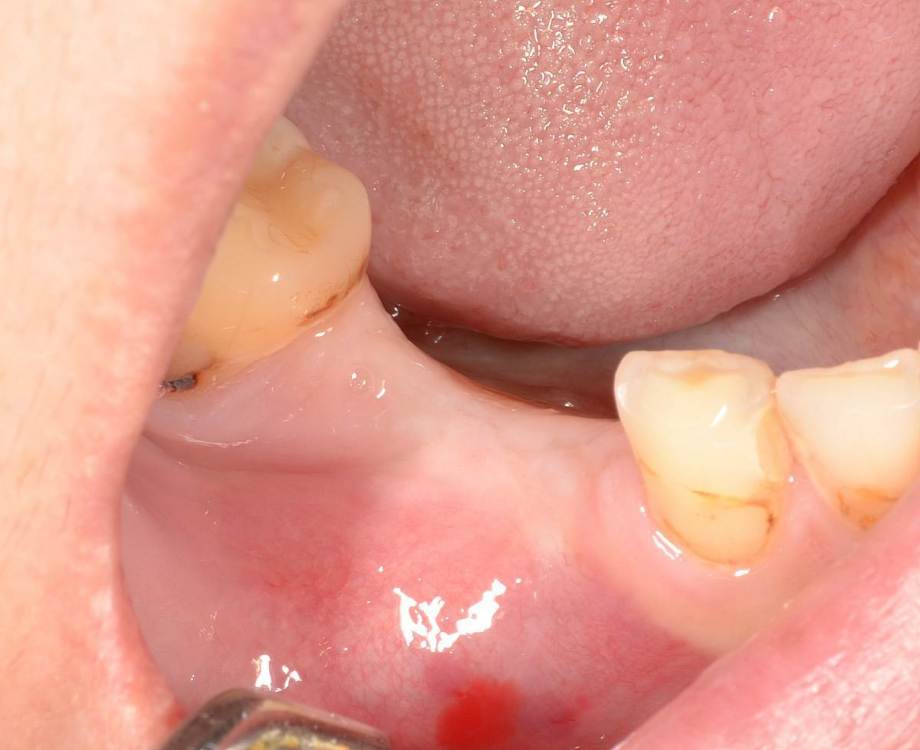

Большой Зеленый Опубликовано 27 мая, 2022 Поделиться Опубликовано 27 мая, 2022 Через 9 лет. Есть немного рецессии.. 2 Ссылка на комментарий

pit Опубликовано 27 мая, 2022 Поделиться Опубликовано 27 мая, 2022 4 часа назад, Большой Зеленый сказал: Через 9 лет. Есть немного рецессии.. Это связано исключительно с вестибулярной позицией импланта. Это как раз к вопросу про те минимальные 2мм до вестиболярной стенки, вне зависимости есть она или ты ее создаешь. Ссылка на комментарий

Большой Зеленый Опубликовано 27 мая, 2022 Поделиться Опубликовано 27 мая, 2022 4 часа назад, pit сказал: Это связано исключительно с вестибулярной позицией импланта. Это как раз к вопросу про те минимальные 2мм до вестиболярной стенки, вне зависимости есть она или ты ее создаешь. С тех пор я стал хитрее умнее и опытнее ))) 1 час назад, alboard сказал: А в чем смысл ее сохранности, если препарируя под имплантат вы все равно ее в большинстве случаев сносите? Первичная стабильность импланта зачастую достигается только перегородкой.. Ссылка на комментарий

Женька Опубликовано 27 мая, 2022 Поделиться Опубликовано 27 мая, 2022 @Большой Зеленый это вроде ваш старый кейс? напомните пожалуйста, тут присыпка+мембранинг вестибулярно и вестибулярным лоскутом слегка послабленным всё закрыли? Ссылка на комментарий

Большой Зеленый Опубликовано 28 мая, 2022 Поделиться Опубликовано 28 мая, 2022 12 часов назад, Женька сказал: @Большой Зеленый это вроде ваш старый кейс? напомните пожалуйста, тут присыпка+мембранинг вестибулярно и вестибулярным лоскутом слегка послабленным всё закрыли? Да все так и есть как Вы и описали. Работе почти 10 лет. Присыпка мп3 от остеобила сверху "ильгамовская" губка . Считаю что результат вполне удовлетворительный. Рецессия обусловлена как уже сказали выше вестибулярным положением импланта ,ну и недозаглублен чуток. Ссылка на комментарий